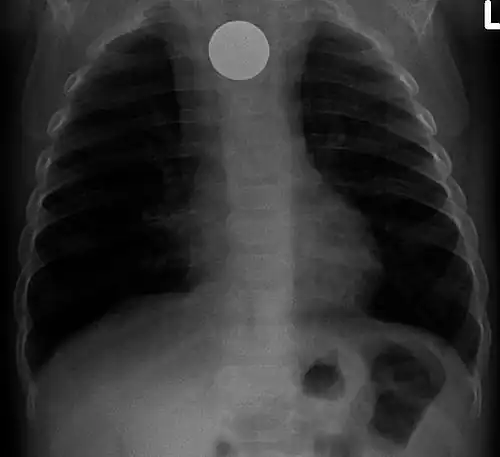

Chest radiograph showing a Venezuelan 25 cent coin lodged in the upper esophagus of a 9-year-old girl. -

A coin seen on AP CXR in the esophagus -

If the person who swallowed the foreign body is doing well, usually an x-ray image will be taken which will show any metal objects, and this will be repeated a few days later to confirm that the object has passed all the way through the digestive system. Also it needs to be confirmed that the object is not stuck in the airways, in the bronchial tree.